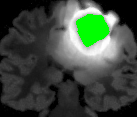

In Fig. 12, we show several tumor segmentation results for all data types.

In Table II, we compare results obtained using different descriptor structures:

patch-based [48], superpixel-based [54],

and superpatch-based (= pixels).

We use the Dice coefficient [55] as evaluation metric,

measuring the overlap between the automatically segmented structure and the ground truth.

The superpixel-based approach

appears very limited since it fails at capturing the tumor context and their location in other images.

Regular patches are also limited in this context, due to the variations in the structure shapes.

Superpatches provide a robust descriptor, since they follow image intensities and capture the superpixel neighborhood,

leading to more accurate segmentation.

These experiments demonstrate that superpatches within the SPM framework provide fast and accurate segmentation results

even on non-registered multi-modal images with poor resolution.